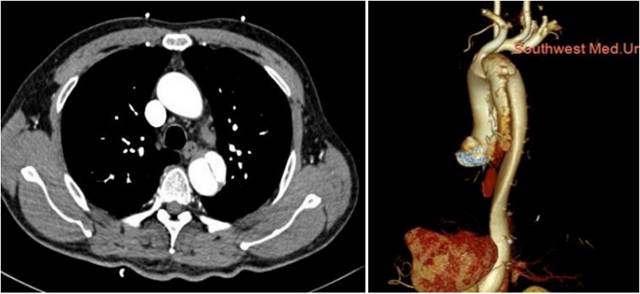

术前检查

张三的家人迅速将他送往西南医科大学附属中医医院,这一举动挽救了他的生命。接诊医生通过对症状的判断迅速启动了胸痛三联征“一站式”CT检查(这是一种通过注射造影剂进行的CT检查技术,可以详细观察胸部大血管的结构)。

经过检查,医生迅速诊断出张三患有主动脉夹层,需要立即行手术干预。最终张三接受了手术治疗,成功挽救了生命。如果没有及时的“一站式”CT检查,他的情况会迅速恶化,将危及生命。